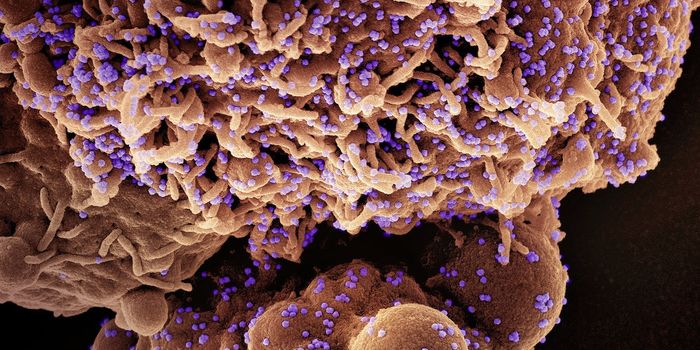

APR 29, 2020Clinical & Molecular DXThe coronavirus disease 2019 (COVID-19) is caused by severe acute respiratory syndrome coronavirus 2 (SARS-CoV-2). Incre ...

APR 01, 2020Clinical & Molecular DXResearchers have begun efficacy testing for a new SARS-CoV-2 diagnostic kit that claims to be able to test for COVID-19 ...